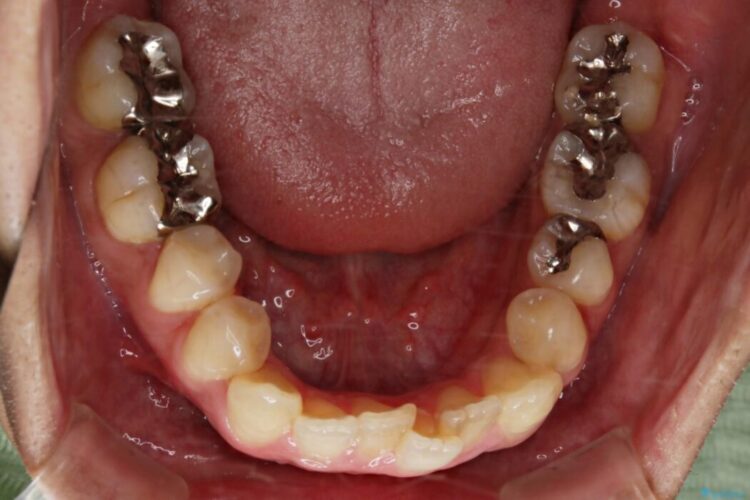

歯列のガタガタと飛び出ている前歯を治したいとのことで来院されました。

装置の範囲内で可能な限り前歯の位置を動かし整えるため、マイクロインプラントを用いて遠心移動をする歯列矯正を計画しました。

本症例では上顎前突(出っ歯)や歯列のがたつきを改善するスペースを確保するために、歯を遠心移動をサポートすることができるマイクロインプラントを用いたゴムかけを行っていただきました。

それにより従来の矯正治療と比べましても効率的に歯の移動を行えるため、非抜歯の場合でも歯列を整えることが可能となります。